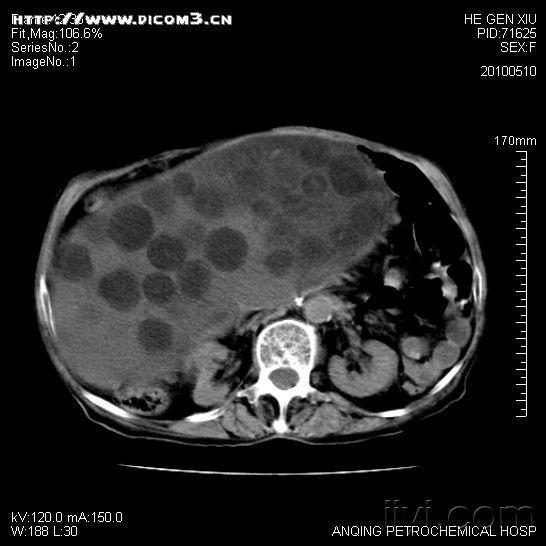

军医提醒:生熟案板不分开 小心脑包虫病找上门!![[读片]腹部病变/ct及/20100510](http://iiyi2.120askimages.com/forum/2010/05/10/1005102002f6ec759dedc03a17.jpg)

[读片]腹部病变/ct及/20100510